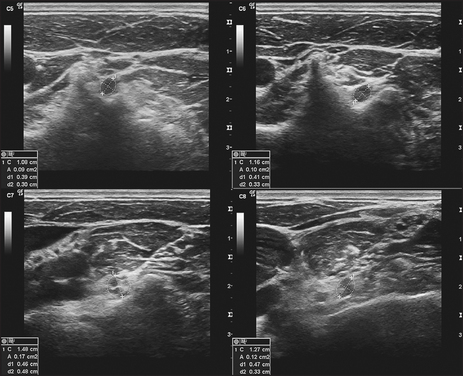

Figure 34.19 C8 nerve. Transverse sonograms of the right C5–C8 ventral rami demonstrating the measuring calipers of the ellipse function at the locations used to measure the cross-sectional area of each ventral ramus as it exits adjacent to the transverse processes. (Haun DW. Ultrasound. Medicine & Biology 2010; 36(0): 1422–1430.)